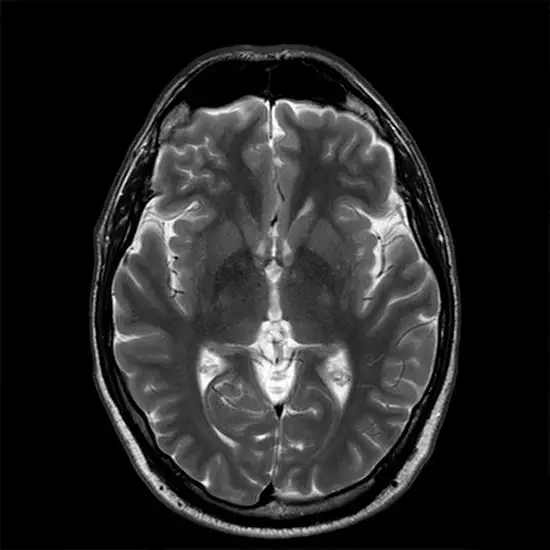

MRI Cranium is a non-invasive imaging procedure that obtains detailed images of the brain and brain stem. It is also known as Brain MRI or cranial MRI. It combines the images and obtains the 3-D images of internal structures and diagnoses the problems in small structures of the brain such as the pituitary gland and brain stem.

MRI Cranium is a Magnetic Resonance Imaging non-invasive medical diagnostic tool used to obtain detailed images of the brain and brain stem. MRI Cranium is used to show abnormalities in the brain like stroke, multiple sclerosis, trauma, infection,  masses etc.